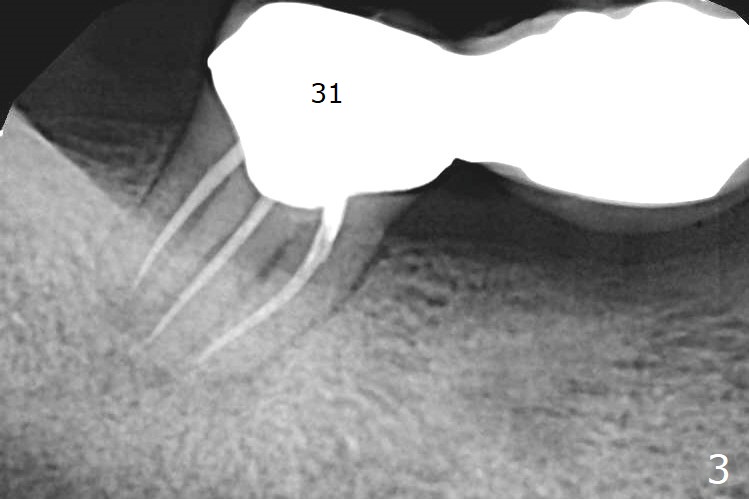

A 66-year-old man has asymptomatic distobuccal (DB) root fracture for ~ 3 years (Fig.1 (>) 2). After #14 implant with limited (M) ortho and 27 and 31 RCT (Fig.3,4), he agrees to have #2 and 3 implants. The tooth #2 has palatal fistula and is tender. Take preop photos. CT should reveal extensive bone loss. Use PRF/sticky bone or GEM21S (if venopuncture is hard) for repair. Save bone from #3 osteotomy for #2 bone graft. Use a special suction with trap after granulation tissue removal.